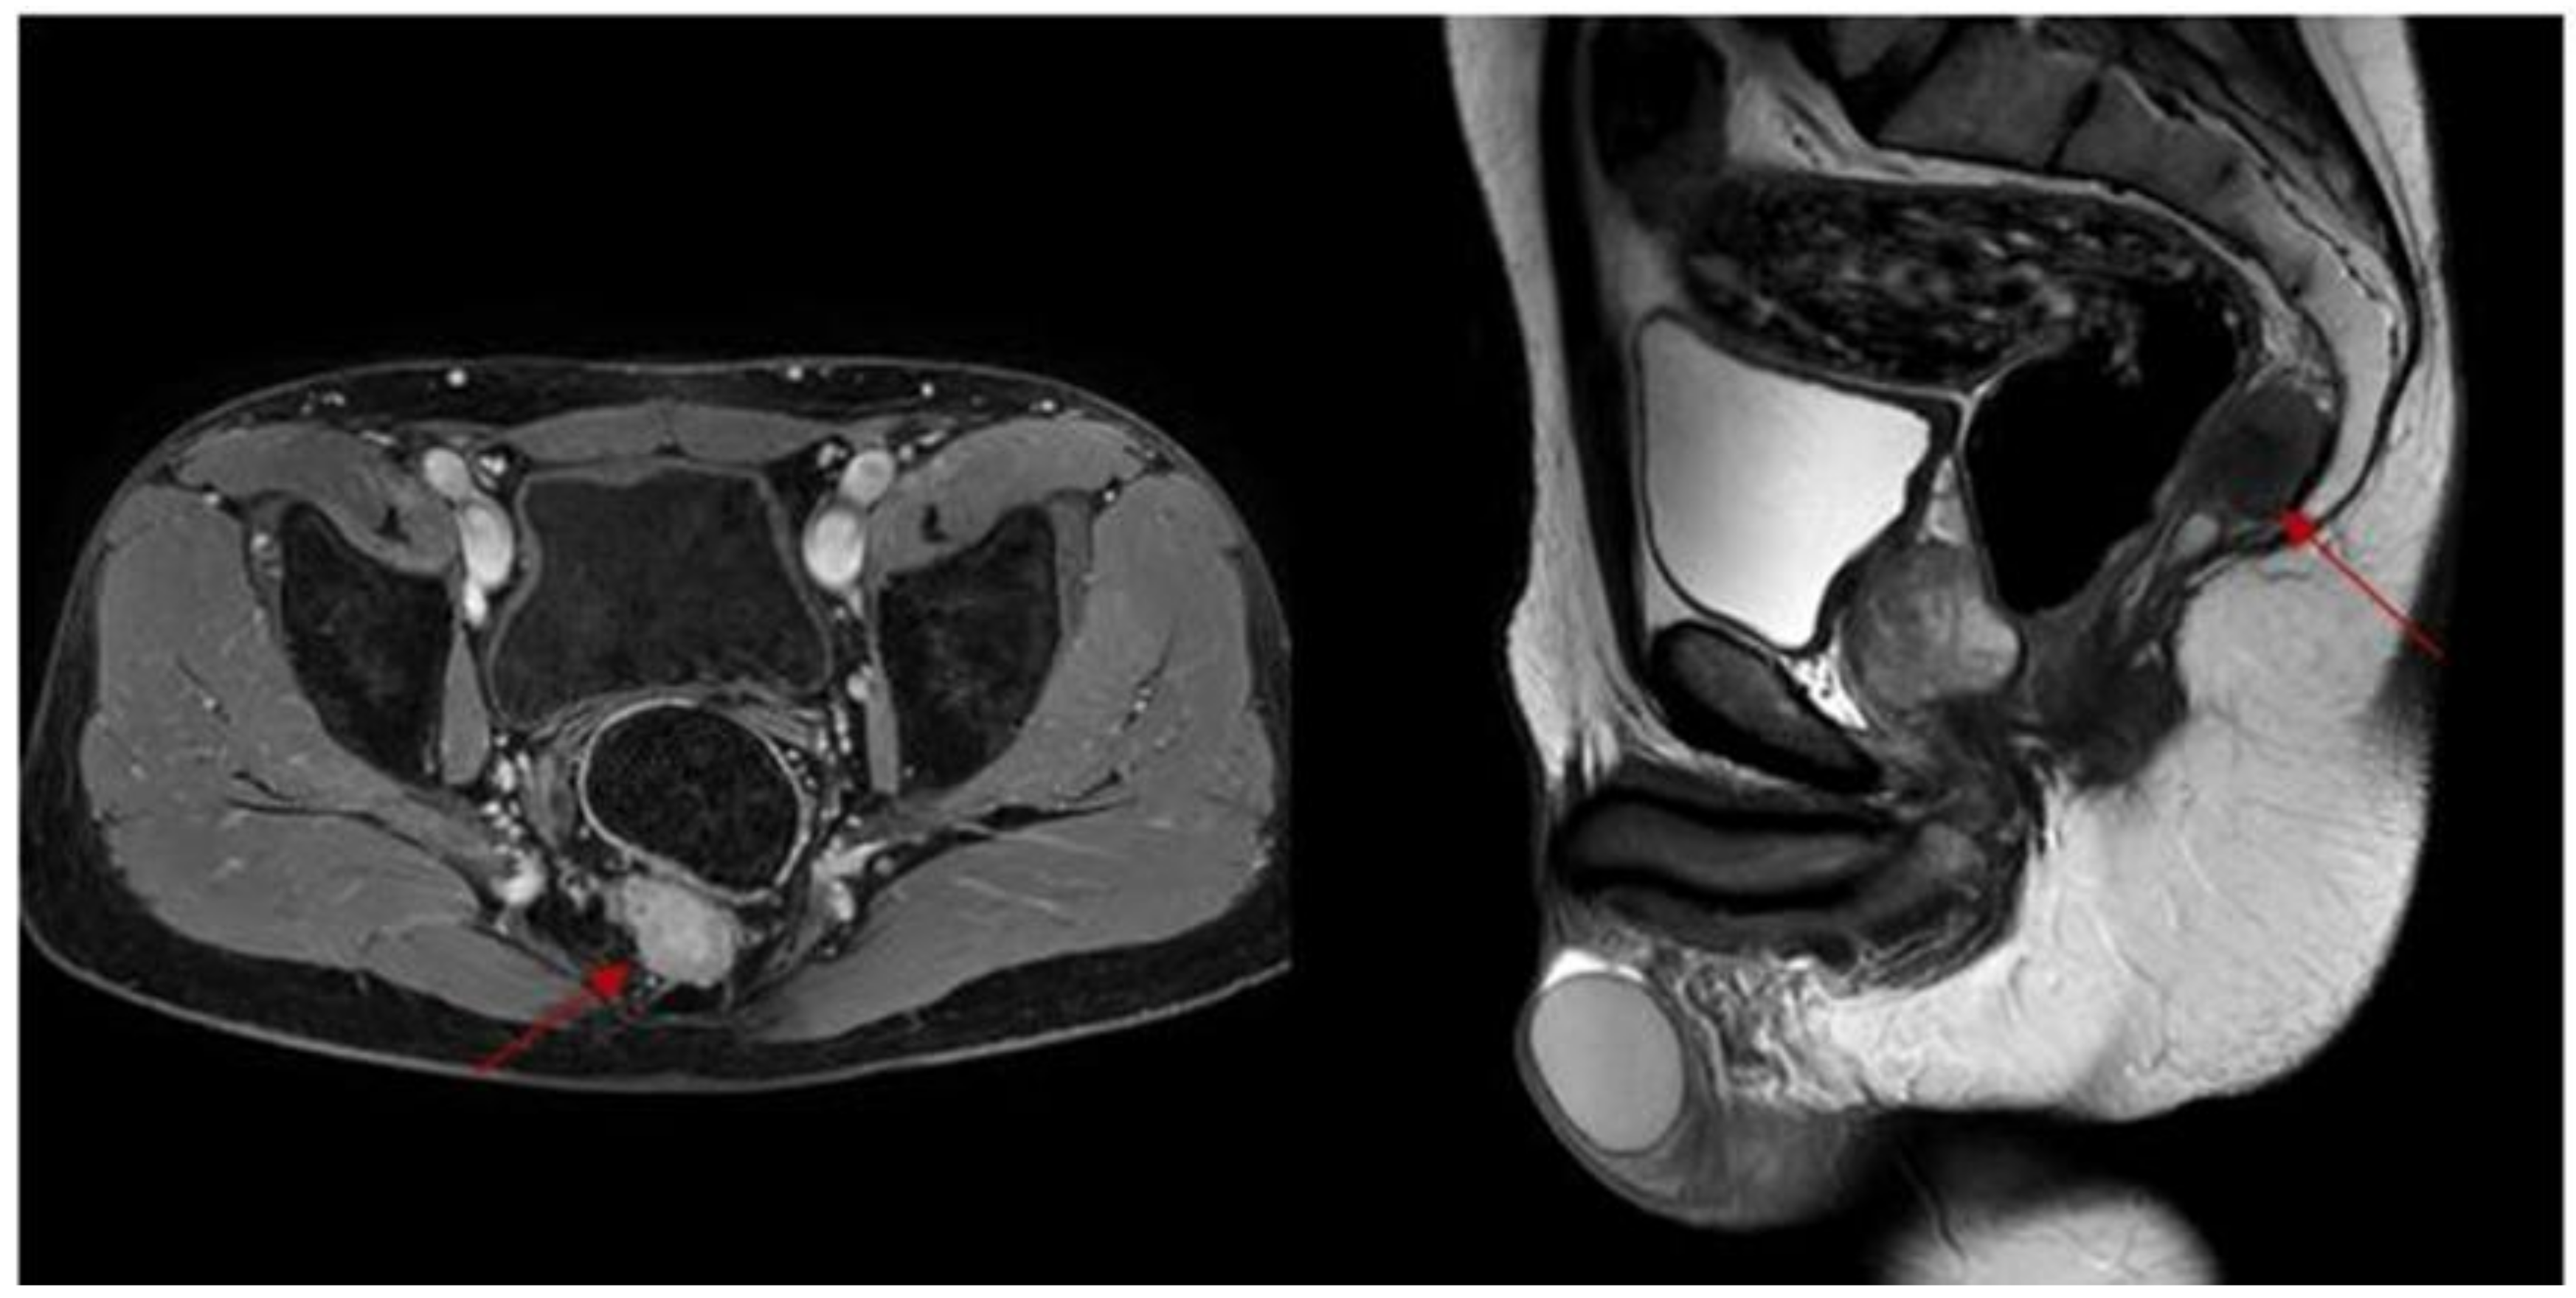

2. Case Report